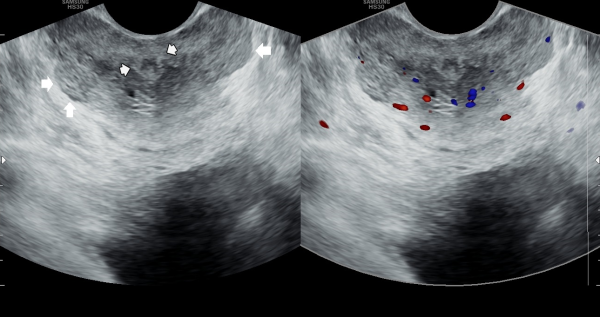

오래전부터 배뇨장애와 빈뇨 및 급박뇨등으로 다른 비뇨기과에서 약물 투여를 했으나 증상의 호전이 없다고 내원 당일 검사한 고환내 다량의 미석증이 관찰된 초음파 사진입니다.

This is an ultrasound image taken on the day of the patient’s visit, who reported long-standing urinary symptoms such as voiding difficulty, frequent urination, and urgency, with no improvement despite medication from other urology clinics. The scan shows a large amount of microcalcifications within the testes.

주2회 전립선의 표적 치료후 고환의 미석증이 줄어 들고 있는 경직장 전립선 초음파 검사 사진

Transrectal ultrasound image showing a reduction in testicular microlithiasis after twice-weekly targeted prostate treatment.

The ultrasound image on the left shows the initial examination, where testicular microlithiasis (tiny calcifications) was present.

The ultrasound image on the right is a follow-up study after several months of targeted therapy to the vas deferens, ejaculatory ducts, seminal vesicles, and prostate, twice a week.

The follow-up scan demonstrates that the previously noted microlithiasis has improved, suggesting that the targeted treatment contributed to the restoration of testicular health.

We hope this evidence may help inform colleagues and patients worldwide that such cases of testicular microcalcification, associated with chronic prostatitis or seminal tract obstruction, can improve through this approach.